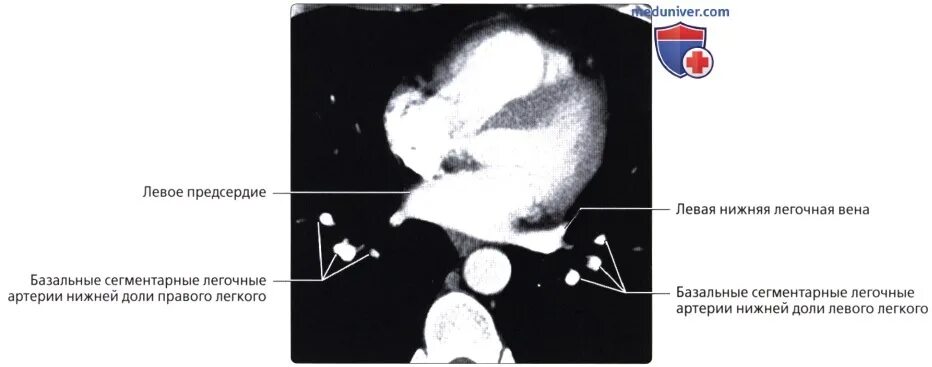

Легочный ствол легкого